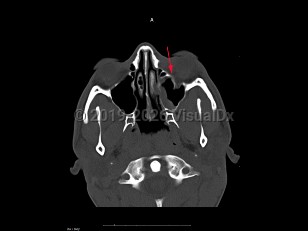

Imaging Studies image of Blow-out fracture of orbit - imageId=7888574. Click to open in gallery.  caption: '<span>Axial CT sequence demonstrates  a depressed fracture of the inferior wall of the orbit. On soft tissue  windows there is a small left maxillary hemosinus.</span>'

Axial CT sequence demonstrates a depressed fracture of the inferior wall of the orbit. On soft tissue windows there is a small left maxillary hemosinus.